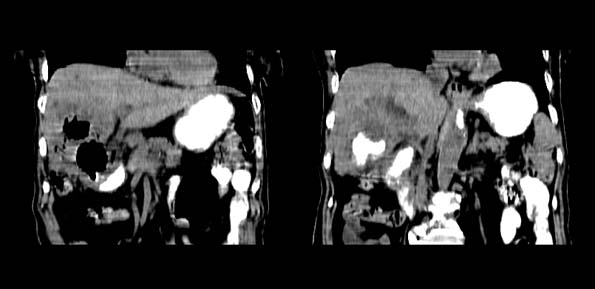

以下是引用bailaode在2008-6-12 22:10:00的发言:[br]资料中未提及患者有无急腹症体征,这个很重要。[br] ct表现:肝内境界模糊之低密度灶,内有含对比剂之液气平面.(提示肝内病灶与胃肠道沟通) [br] 1、根据“长城干红 ”所提供的资料“患者,女,74岁,黑便月余,消瘦,一般状况差,白细胞1万四千”,是否可认为是个慢性病程?那么我首先考虑:十二指肠结核,十二指肠--胆管瘘,继发胆道逆行感染肝脓肿形成。[br] 2、如有急腹症体征则考虑:十二指肠溃疡穿孔?十二指肠占位伴穿孔?

以下是引用拾荒者在2008-6-13 22:13:00的发言:[br]病灶与升结肠、肝脏及十二指肠关系密切,且结肠降段见造影剂影,支持结肠与十二指肠瘘形成,原因及原发病在哪不好定,不过,虽说有风险,但还是应该手术治疗,单纯抗感染估计不行。